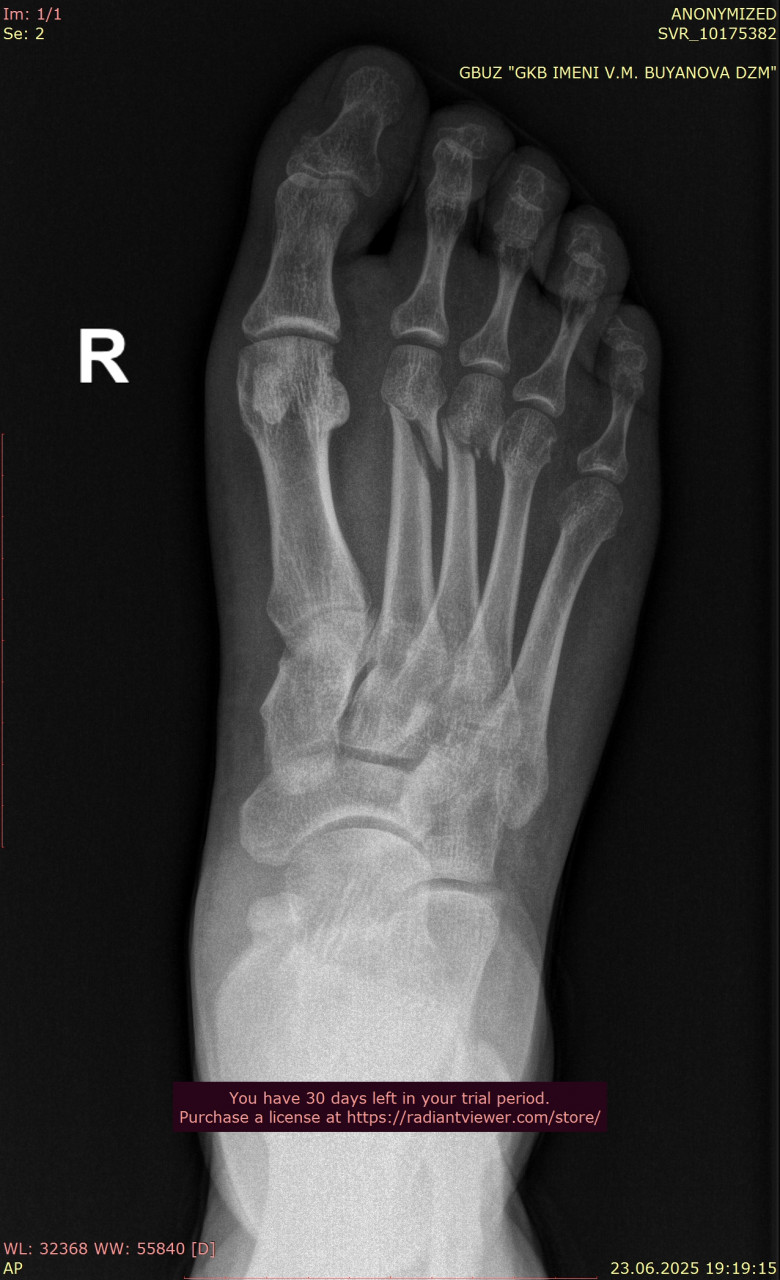

Посмотрите, пожалуйста, снимки стопы и лодыжки от 25.08.2025, перелом был 9 недель назад, 23.08.2025, прикрепляю только прямую проекцию так как лимит сайта 3 файла. Зажили ли переломы, можно ли начинать ходить без дополнительной опоры? Мне 38, мужчина, рост 179, вес 64. Мне говорили что на снимках есть артроз суставов. Подскажите, пожалуйста, насколько он выражен, опасно ли это? Может нужны процедуры, лекарства?

Андрей Павлович, Большое Спасибо Вам за ответ! Прикрепляю недостающий снимок стопы от 23.06.2025, когда был перелом, и снимки лодыжки от 25.08.2025, вчерашние, здесь тоже лимит файлов, снимки лодыжки от даты перелома могу прикрепить в следующем комментарии, и если Вас не затруднит, подскажите, пожалуйста, сильный ли у меня артроз суставов для возраста 38 лет?

Сравнивая ваши снимки от 23.06 и 25.08:

- Линии переломов на костях стопы и области голеностопного сустава больше не прослеживаются чётко, видна формирующаяся костная мозоль – это признак заживления.

- Смещения отломков нет, контуры выровнены, что говорит о правильном срастании.

- Для срока 2 месяца после перелома динамика положительная, основные признаки консолидации присутствуют. Обычно к этому времени разрешают постепенную нагрузку, но полное снятие опоры (ходьба без костылей, тростей) должно быть постепенным и согласовано с вашим травматологом.

По поводу артроза, на рентгене действительно заметны начальные изменения в суставах стопы (сужение суставных щелей, небольшие краевые разрастания), но они умеренные и для 38 лет не критичны. Такие изменения часто встречаются после травм и нагрузок, но выраженного деформирующего артроза нет.